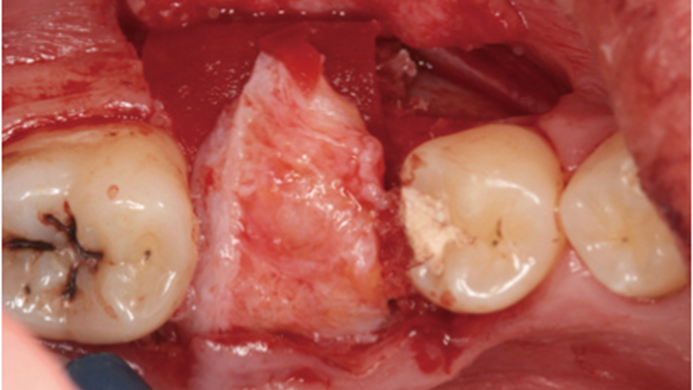

“Thin ridge expansion with minimally invasive surgery!

Use SmarThor & AnyRidge to place a wider diameter implant with minimal drilling after ridge splitting, even in thin ridge under 2mm! “

Clinical case: Ridge splitting technique using SmarThor + AnyRidge as expander

- Courtesy of Dr.Kwang-Bum Park, Korea -

AnyRidge, ridge splitting, GBR, Dr. Kwang-Bum Park, mandibular posterior, SmartThor, Mega-Oss, thin ridge, bone regeneration

AnyRidge implant system. SmarThor, Mega-Oss